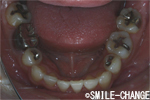

| 歯形・咬み合わせの採得、お口の中とお顔の写真撮影、顎関節のチェックなどをして、 噛み合わせや骨格のズレ、歯や骨の様子を細かく調べて、分析を行います。 (所要時間30〜40分) |

![]() ![]() ![]() ![]() ![]() |

![]() ![]() ![]() ![]() |